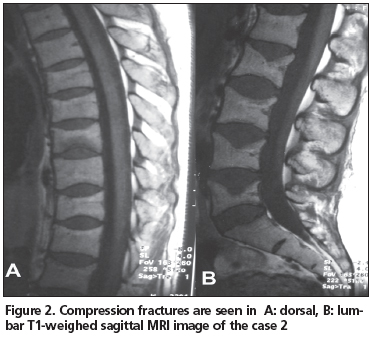

Twenty-six years old female patient was admitted to our rheumatology out-patient clinic with the complaint of low back pain. Her pain started 4 months ago, immediately after delivery of her first child. The pain was aggravated by physical activity and diminished with nonsteroidal antiinflamatory drugs. Lumbar MRI was carried out with the prediagnosis of lumbar disc herniation. Vertebral deformities due to compression fractures were discovered both in the dorsal and lumbar vertabrae (Figure 2), and the patient was hospitalized for differential diagnosis.